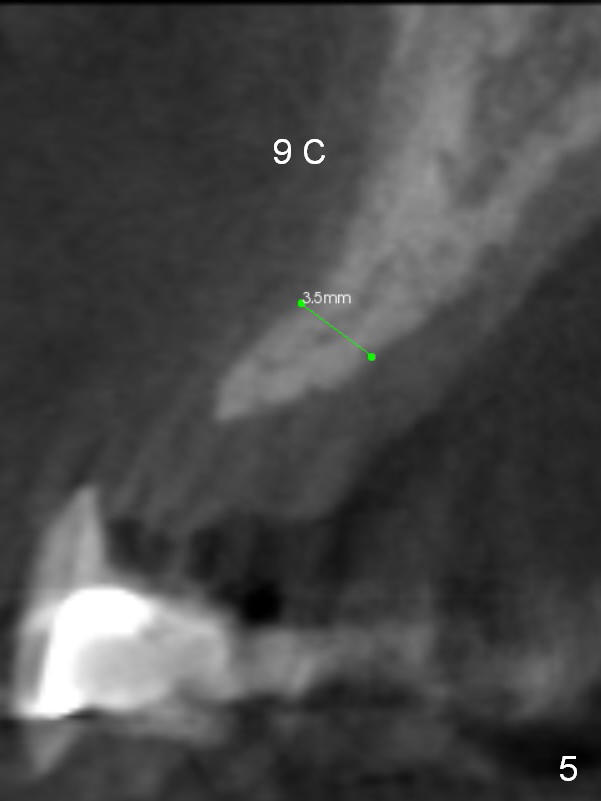

A 53-year-old man chips porcelain of the upper anterior bridge after implant placement at #14 and 15. Since he will return to home country for visit in the next few months, he is eager to restore the anterior restoration. Two of the abutments (#10, 11) appear to have severe bone loos (Fig.1,2 *). It does not seem to be a ideal treatment plan to redo the bridge. The edentulous ridge is atrophic at #8 and 9. It appears that 2.5 mm 1-piece implants (Fig.3,4) fit better than 3.0 mm one (Fig.2). There is a buccal concavity at #9 (Fig.1 red dashed line). The 2.5 mm implant at #9 should be placed between the Incisive Canal (Fig.1 I) and the buccal concavity (Fig.4). The ridge at the buccal concavity is not suitable for implant placement (Fig.5). The palatal plate (Fig.2 P) is usually denser and thicker than the buccal one. The osteotomy for the implant is initiated palatally; the implant is placed below the buccal crest (Fig.2 >). The exposed lingual thread will be covered by bone graft (Fig.3 pink circles) and collagen dressing. Since the ridge at #9 appears more atrophic, a 2.0 mm 1-piece implant may be indicated. The bridge will be sectioned between 7 and 8 and 9 and 10.